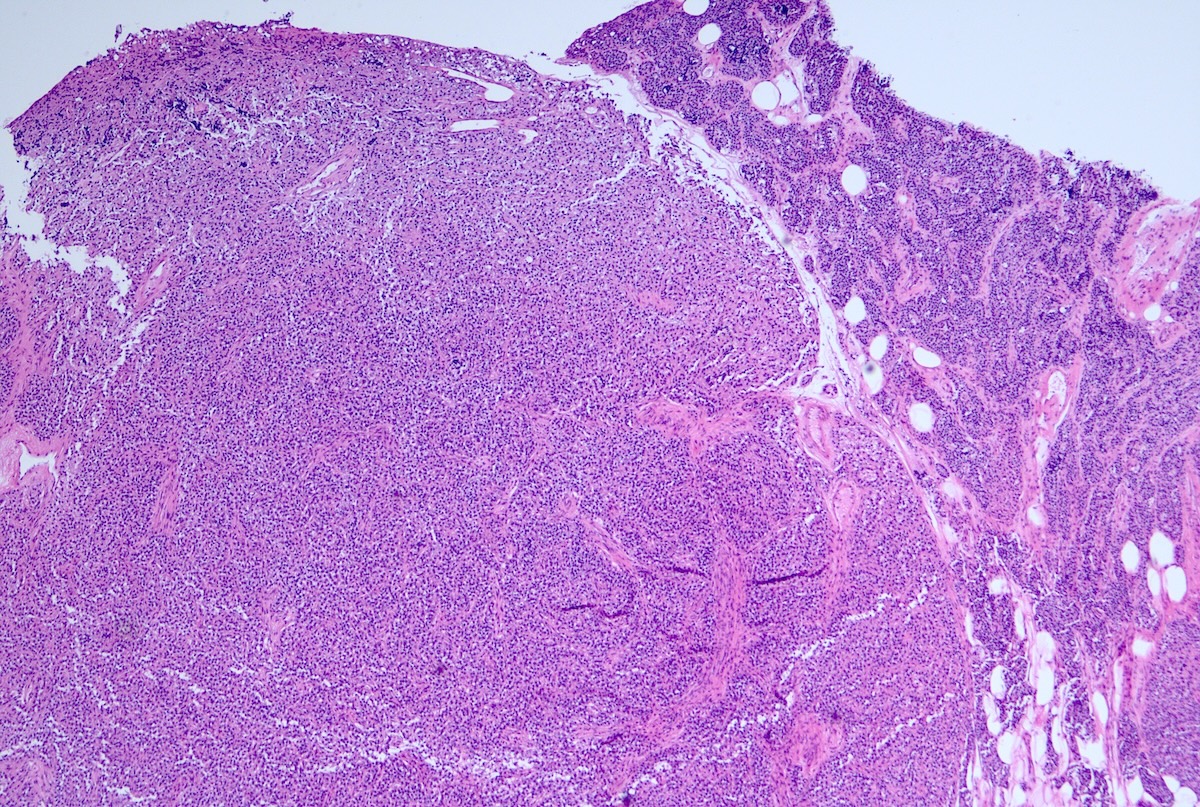

- Pancreatic neuroendocrine tumors

- Well differentiated NETs composed of uniform polygonal cells with eosinophilic or clear cytoplasm, salt and pepper chromatin (finely granular nuclear chromatin) (Arch Pathol Lab Med 2025 Mar 4 [Epub ahead of print])

- Immunohistochemical staining positive for chromogranin A, synaptophysin and neuroendocrine markers (Arch Pathol Lab Med 2025 Mar 4 [Epub ahead of print])

- Some tumors may show vascular invasion or mitotic activity, indicating more aggressive potential

- Diffuse islet cell hyperplasia occurs frequently (World J Gastroenterol 2011;17:137)

- Multiple pancreatic microadenomas or microtumors are a common feature of MEN1 associated PanNETs and serve as a useful clue to the diagnosis of MEN1